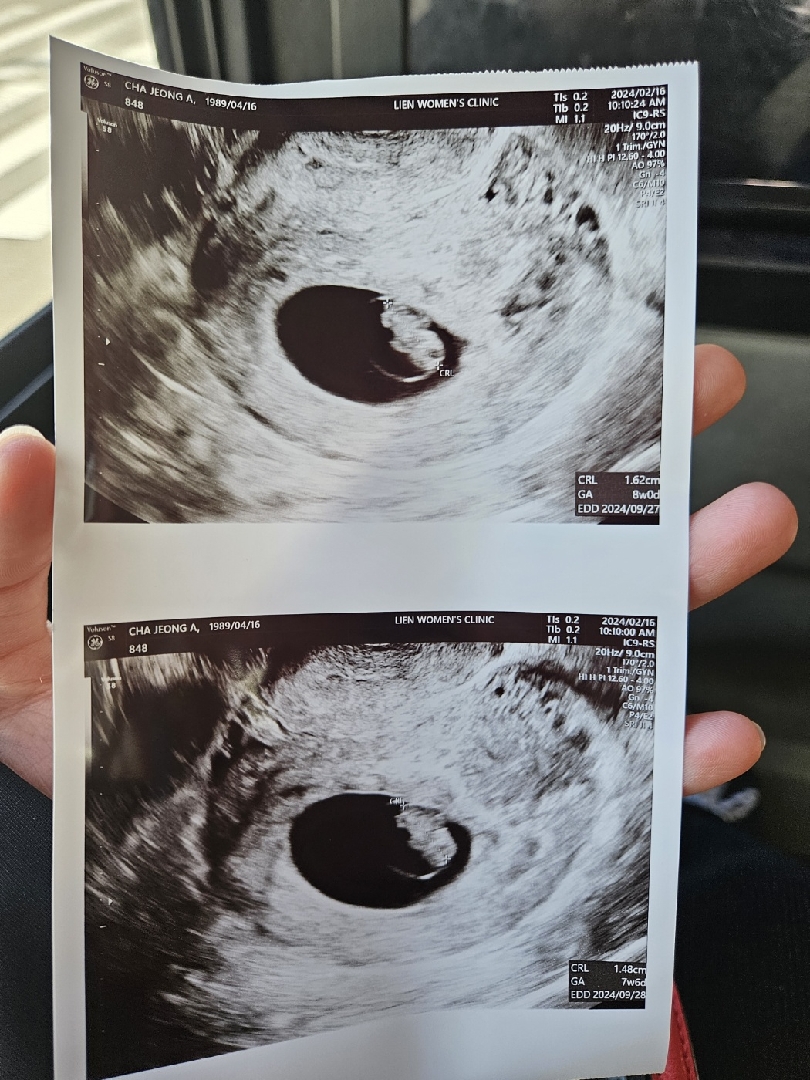

오늘로써 8주차인데 초기 임산부 초음파 2번 사용해서 오늘은 비급여라고 9만원나왔어요 ㅜㅜㅜ 그리고 보건소에서 산전검사했는데 추가로 갑상선이랑 알러지외 더 받아야되는 부분 있다고 해서 피검사랑 초음파 총 19만원 나왔어요 ㅠ 다들 그정도 나가시나요??? 아니면 저만 그런걸까요???

저도 궁금해요ㅠㅠ 처음 임신 확인했을때 5주차에 딱 한번 만원 나오고 7주땐 산전검사 플러스 되서 8만원대 그뒤론 초음파만 보는데 5만원이요ㅠㅠ